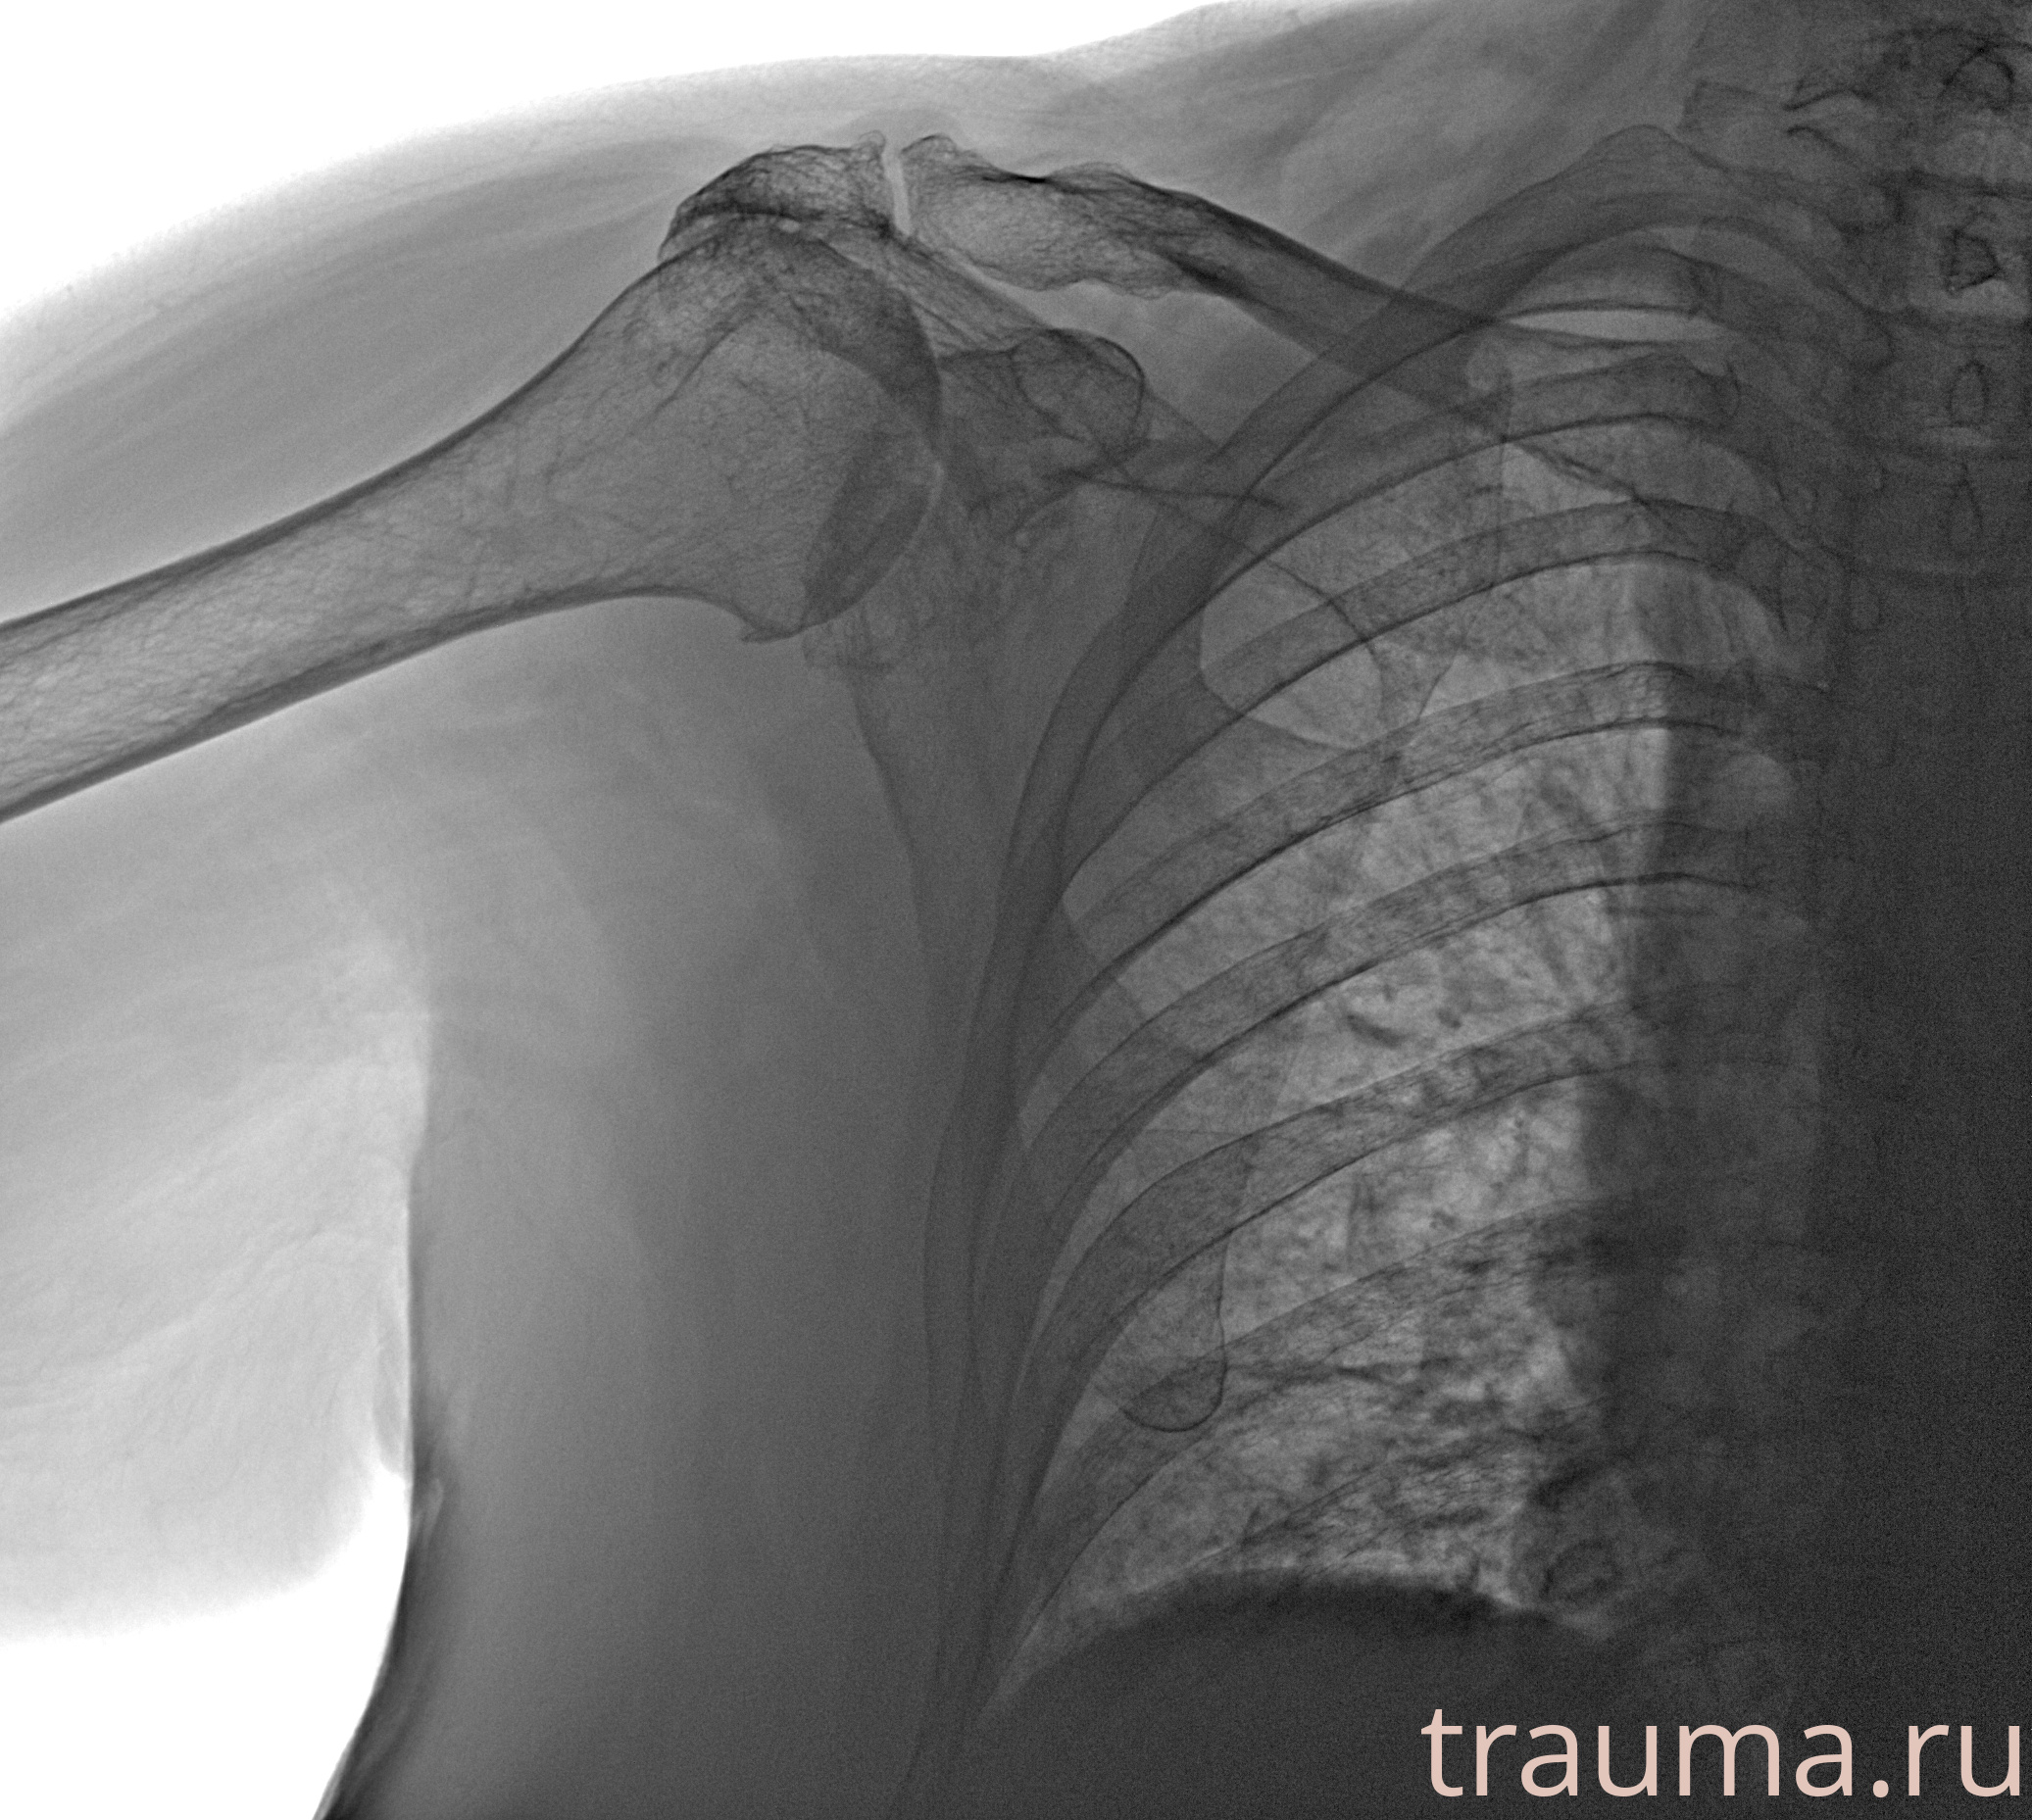

Рентгенограммы

Рентген на дому: по вашему адресу приезжает врач-рентгенолог, травматолог-ортопед с мобильным рентгеновским аппаратом, проводит диагностику травмы или заболевания, делает необходимые рентгенограммы, дает рекомендации по дальнейшему лечению. Получить качественные снимки в домашних условиях возможно благодаря уникальной методике, разработанной МосРентген Центром для института  Склифосовского